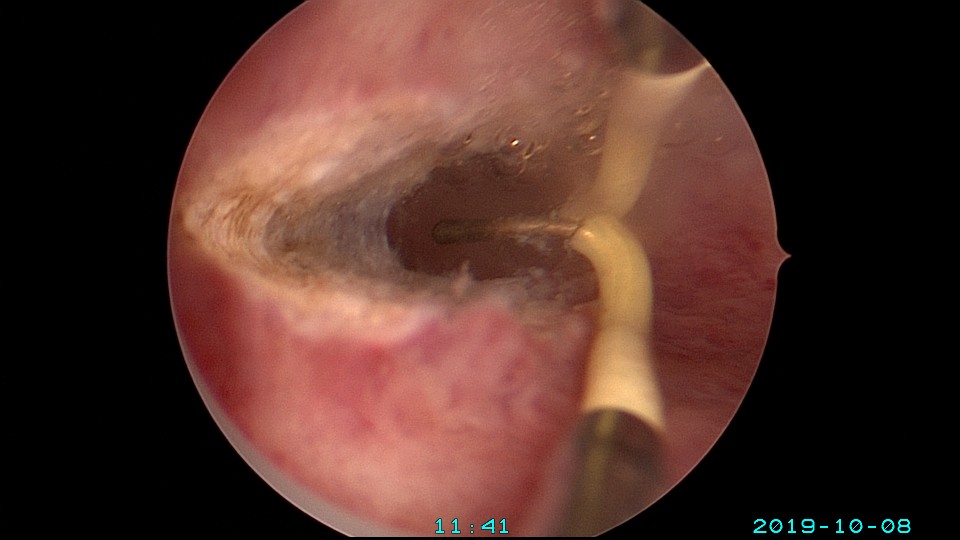

患者27岁,G2P0,人流1次,孕8周胎停清宫1次,绵阳市某医院造影发现宫腔粘连1+月,2019年10月初我院宫腔镜探查,发现宫腔右侧粘连,左侧输卵管开口可见,单极电切分粘,恢复宫腔形态,显露右侧输卵管开口。2019年10月底宫腔镜二探取球囊,宫腔形态正常,双侧输卵管开口可见。2021年10月自然妊娠,稽留流产,我院宫腔镜取胚,2022年再次自然妊娠,足月分泌。现33岁,G4P1。